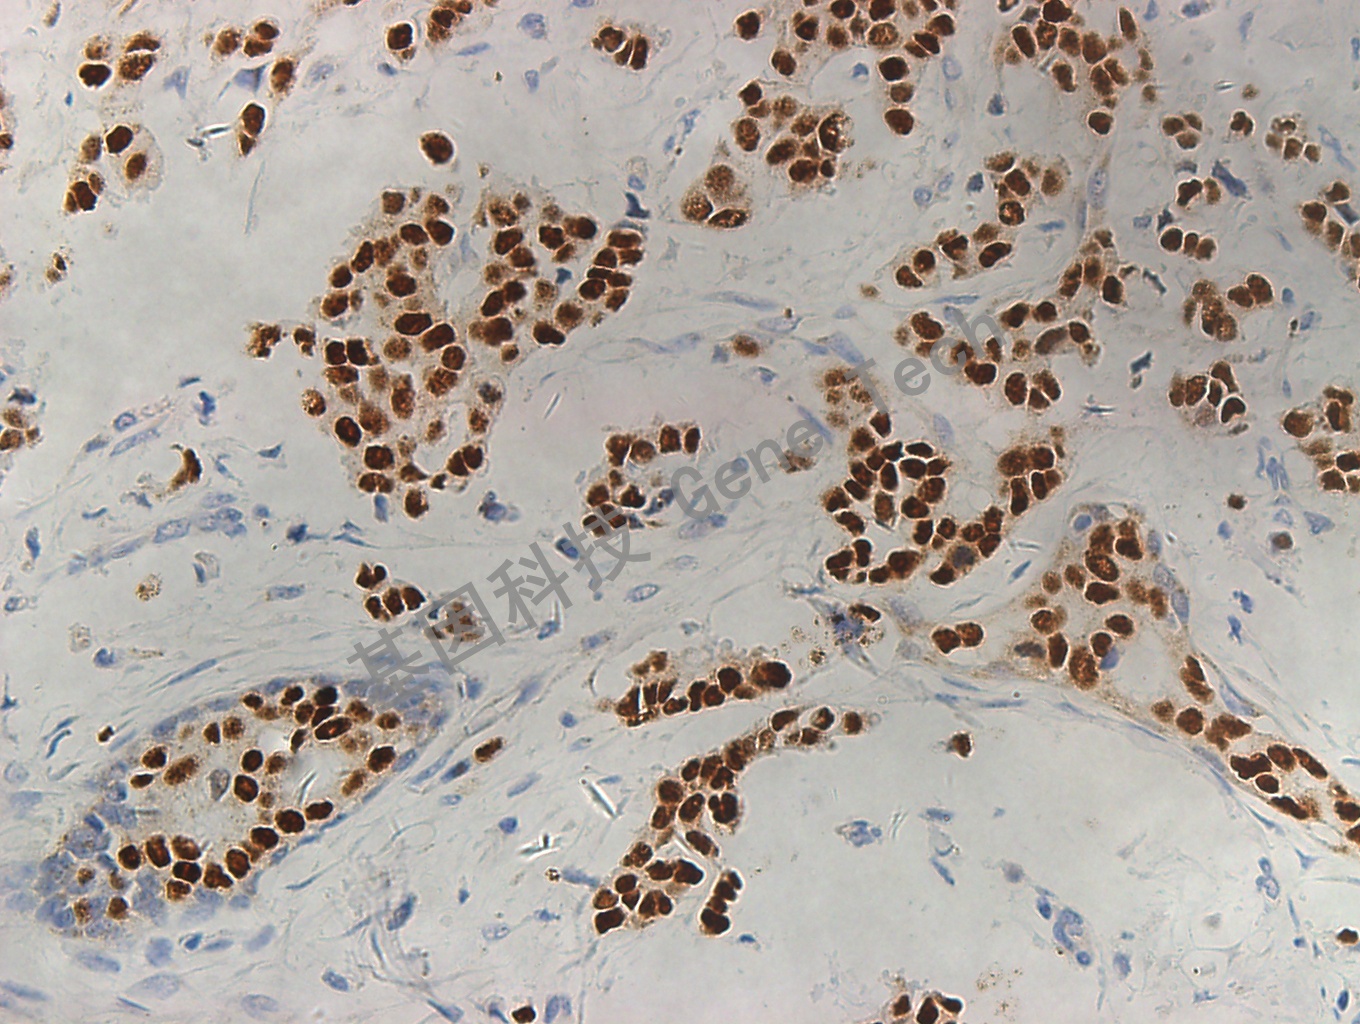

膀胱癌石蜡切片,用 GATA3(GT2187)染色,细胞核阳性,DAB 显色。